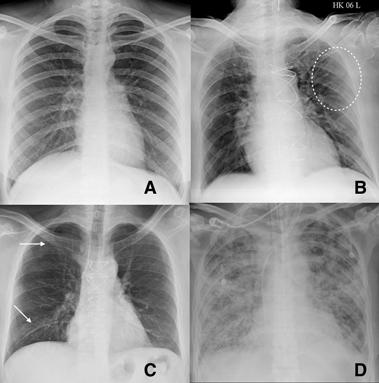

Fig 8 — Serial CXR examinations in a patient showing disease progression. Presentation (A) film had bilateral peripheral hazy opacities that increased on day 7 (B) and became confluent. Further worsening of parenchymal changes on day 11 with the patient requiring extracorporeal membrane oxygenation (ECMO) support (C) with improvement in clinical condition and persistent parenchymal fibrotic infiltrates on day 23 of admission (D). Images courtesy of Dr Amrita Bajaj, Glenfield Hospital, Leicester.

Imaging can play a vital role in assessing the severity of COVID-19 patients. To assess the extent of disease involvement, a simplistic radiographic scoring system was used by Wong et al12. Each lung was graded from 0-4 based on the extent of involvement (0- no involvement, 1- up to 25%, 2- 25-50%, 3- 50-75% and 4 >75% involvement). The scores of each lung were added to get a final score. The severity score of CXR varied over the time and peak severity was seen at 10-12 days from symptom onset (Fig 8). As the disease progresses the GGO are replaced by areas of consolidation that either resolves or worsens to give ARDS picture11 (Fig 9). Various CT severity scores have shown good correlation with clinical severity of disease20 21. The degree of lung inflation at the initial CT can also predict adverse outcomes in patients with COVID-1922

Fig 9 — Serial CXR examinations in a patient who succumbed to the infection. This patient came in with severe respiratory distress and was put on ventilator support early in his admission. ECMO therapy was also started (A) with bilateral parenchymal consolidation. Patient kept deteriorating on ECMO (Day 13- B, Day 18 C and Day 27- D) and succumbed to the disease. Images courtesy of Dr Amrita Bajaj, Glenfield Hospital, Leicester.